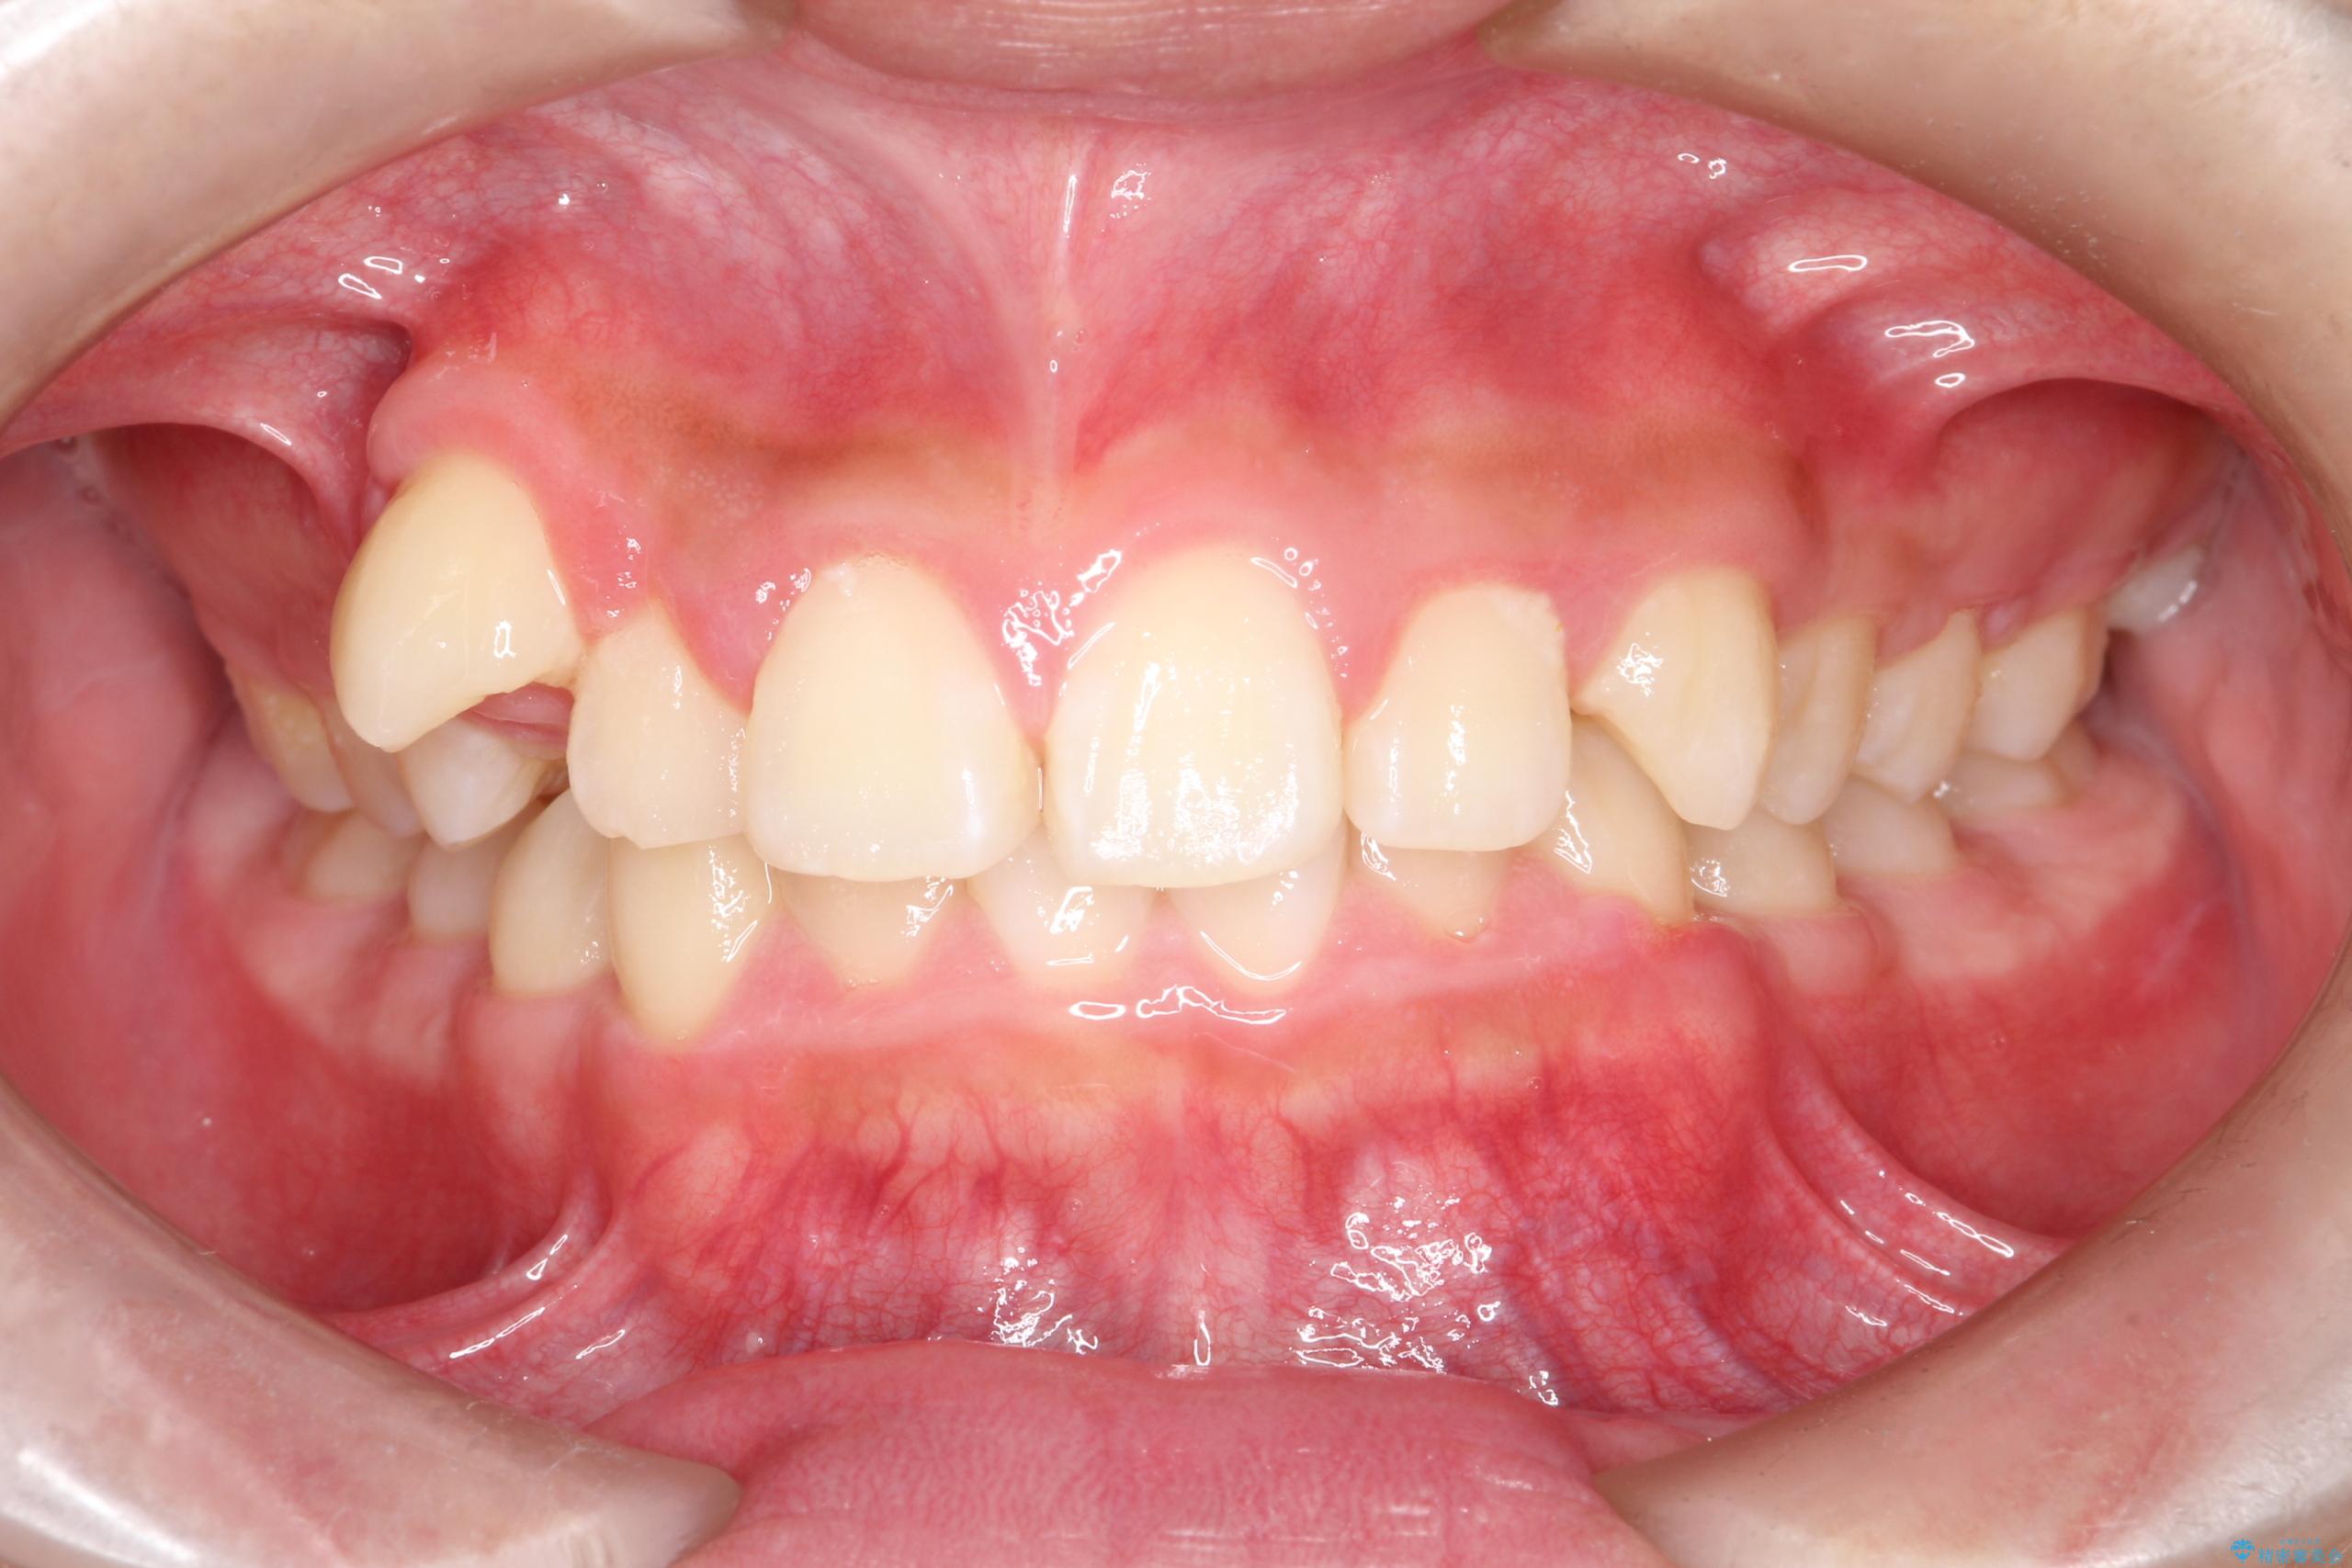

八重歯・歯並びのデコボコとディープバイトを改善した抜歯ワイヤー矯正症例

- 八重歯と咬み合わせを治したいを主訴にご来院された患者様です。

矯正の精密検査の結果上顎左右4番の計2本を抜歯し、審美性に配慮したワイヤー矯正装置(審美装置)を用いて治療を行いました。

八重歯などの歯列のデコボコが綺麗に改善され、患者様にも大変喜んでいただけました。また、咬み合わせが深い「ディープバイト」も併せて改善し、見た目だけでなく機能面でもバランスの取れた咬合を獲得しています。